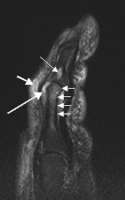

Sagittal magnetic resonance images of the ankle region in psoriatic arthritis. (a) Short tau inversion recovery (STIR) image, showing high signal intensity at the Achilles tendon insertion (enthesitis, thick arrow) and in the synovium of the ankle joint (synovitis, long thin arrow). Bone marrow edema is seen at the tendon insertion (short thin arrow). (b, c) T1 weighted images of a different section of the same patient, before (panel b) and after (panel c) intravenous contrast injection, confirm inflammation (large arrow) at the enthesis and reveal bone erosion at tendon insertion (short thin arrows). -